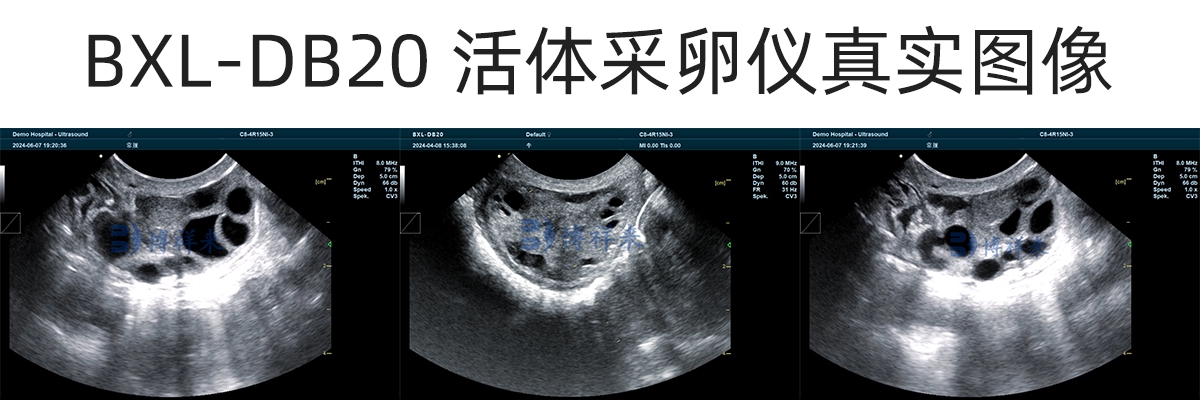

在操作过程中,兽用B超机实时显示卵巢结构和卵泡位置,操作人员在超声引导下,将穿刺针精准进入卵泡,通过负压将卵泡液和卵母细胞吸出,从而完成活体采卵。

牛用B超的清晰度和稳定性,是牛活体采卵成功率的关键基础。

成像清晰度高,能准确分辨卵泡边界

图像延迟低,实时性强

只有在清晰、稳定的超声图像引导下,才能提高采卵成功率,同时降低误穿刺风险。